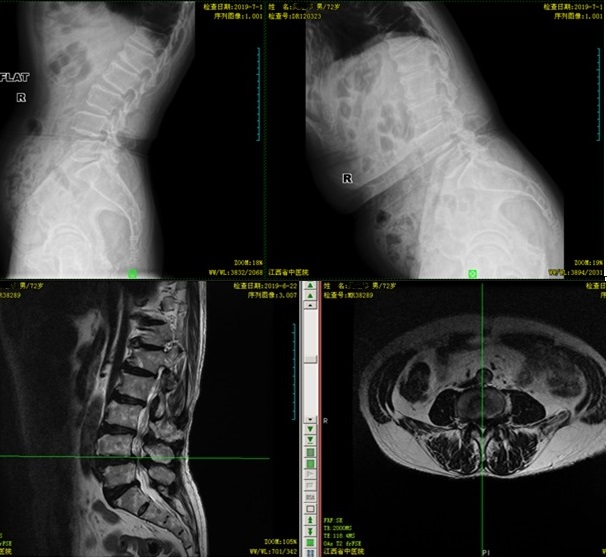

术前DR及MRI:

我们可以清楚的看到,腰椎出现了滑脱,且L4/5椎间盘突出,传统的手术方式需要在患者背部行一长约10cm的开放性切口,且需要剥离大量的肌肉,软组织和损伤椎板及棘突。